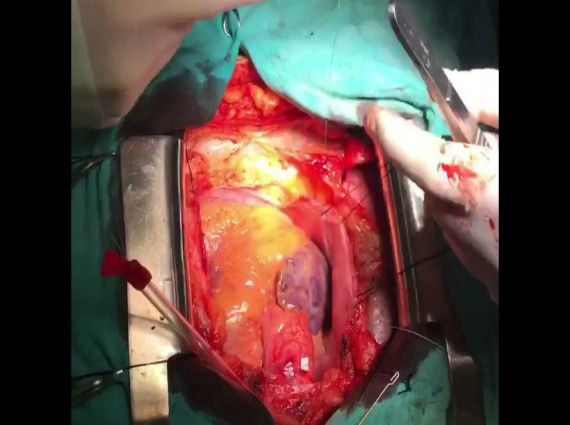

Çocuklarda kalp ameliyatları hem çok zor, hemde her merkezde uygulanamamaktadır. Özellikle kompleks kalp patolojilerinin amaliyatları daha da önem arzetmektedir. Özellikle cerrahi sonrası bakım ve komplikasyonların yönetimi çok daha zor ve önemlidir. Meşguliyeti çok getirisi az olan ameliyat türüdür.

Dünyada en zor ve kompleks ameliyatlar arasında yer almış, risk skorlamasında ön saflarda yer tutmuştur. Doğuştan kalp hastalıklarının %20'si kompleks kardiyak patoloji olup cerrahi tedavileri dışında herhangi bir tedavileri yoktur. Kompleks kardiyak patolojilerin çok önemli bir kısmında birden fazla ameliyat gereksinimi olabileceğini unutmamalıyız. Erken dönemde hatta yenidoğan döneminde dahi ameliyat gereksinimi olabilir. Bazı hastalar 3 yada 4 kez ameliyat gerektirebilir. Bir kısmında erişkin dönemlerinde dahi ameliyat gerektirecek durumlar olabilir.

Bazı durumlarda nihai çözüm kalp transplantasyonu (nakli) olabileceğini bilmemiz gerekir.